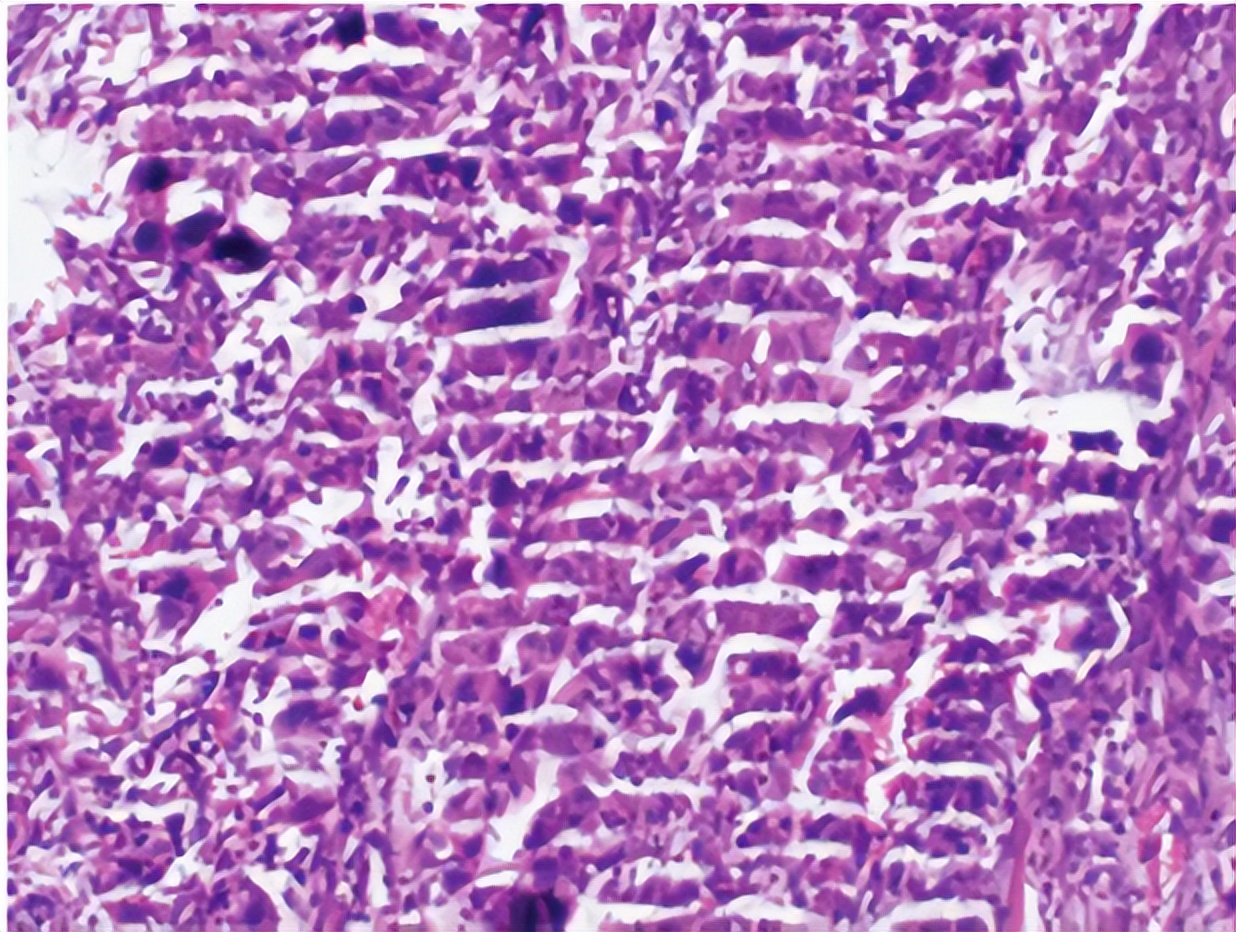

石蜡切片(paraffin section)是组织学常规制片技术中应用最为广泛的方法。石蜡切片不仅用于观察正常细胞组织的形态结构,也是病理学和法医学等学科用以研究、观察及判断细胞组织的形态变化的主要方法,所以广泛地适用于许多学科领域的研究中。

活的细胞或组织多为无色透明,各种组织间和细胞内各种结构之间均缺乏反差,在一般光镜下不易区分;组织离开机体后很快就会死亡和产生组织腐败,失去原有正常结构,因此,组织要经固定、石蜡包埋、切片及染色等步骤制成片子,才能在镜下清晰辨认其形态结构。

石蜡切片法包括取材、固定、洗涤和脱水、透明、浸蜡、包埋、切片与贴片、脱蜡、染色、脱水、透明、封片等繁多步骤;其中切片是决定片子质量好坏的最重要的环节之一。因而影响石蜡切片的因素比较多,本期文章我们归纳了常见切片问题有哪些,以及该如何进行补救。